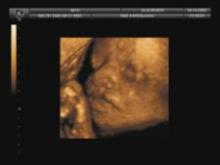

Toshiba will also highlight its 4D volume imaging applications for ultrasound that were designed to improve transvaginal/ob, small parts and abdominal imaging procedures.

The compact ProSound Alpha 7 ultrasound system from Aloka features Directional eFLOW, which visualizes blood flow dynamics from low to high velocity flow reportedly without overlapping and with a high degree of accuracy. Also included are basic imaging performance enhancements with Broadband Harmonics, ExPHD (Extended Pure Harmonic Detection) and high temporal resolution to aid in the diagnoses of fetal heart conditions.